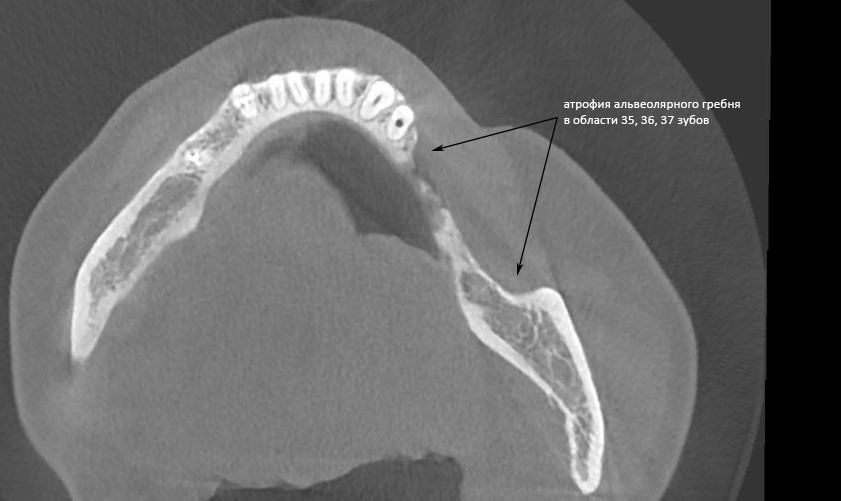

Теперь возьмём клинический случай (нижняя челюсть, отсутствия 35, 36, 37 зубов, атрофия альвеолярного гребня по ширине):

и рассмотрим его через парадигму методологического редукционизма. Или, если хотите, сквозь Бритву Оккама.

Мы имеем относительно небольшой дефект, не позволяющий, однако, установить имплантаты правильного размера в правильное положение. И два варианта остеопластической операции, НКР и АТККФ.

Первый вариант — это направленная костная регенерация (НКР) и её модификации. Этот метод относительно прост, но требует использования биоматериалов (барьерной мембраны и ксенографта). Кроме того, нам нужна аутокостная стружка, чтобы сделать микс с ксенографтом (почему это необходимо — смотрите тут). То есть, рану всё равно придётся открывать достаточно широко. Ну и, наконец, при такой форме альвеолярного гребня одномоментная имплантацию будет представлять сложности — даже в плане подготовки лунок.

Итого: метод менее травматичный, но более дорогой, одномоментная имплантация представляет технические сложности.

Второй вариант — это пересадка костного фрагмента (костного блока) в область дефекта альвеолярного гребня. Методика не требует использования биоматериалов, но нуждается в донорском участке. Сам забор аутографта масштабнее и травматичнее, чем при НКР. Хорошо зафиксированный на принимающем ложе костный блок позволит нам без труда подготовить лунки и установить имплантаты правильного размера в правильное положение.

Итого: значительно более дешевая методика при сопоставимой травматичности, позволяющая легко провести одномоментную имплантацию.